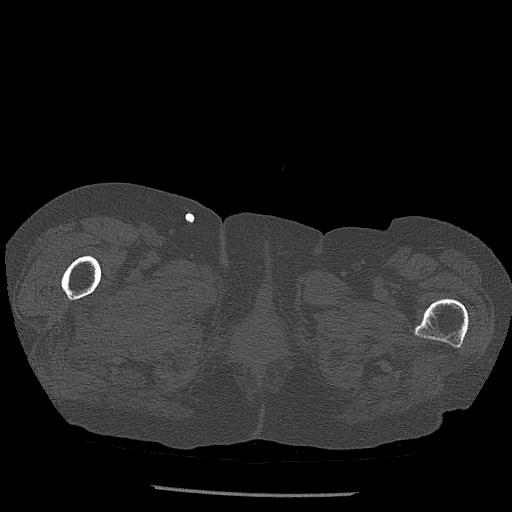

100703 1/27 両股正面+軸 1/29 両股正面+軸 94歳女性 パンソンロン